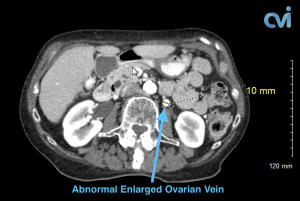

Magnetic resonance imaging (MRI) and computed tomography (CT) is another method to diagnose pelvic congestion syndrome. Our practice requires a CT of the Abdomen and Pelvis with contrast prior to treatment. This allows us to see where the varicose veins are coming from so that we can plan and do the appropriate treatment. Sometimes there are abnormal pelvic veins in addition to the ovarian veins that need treatment. Sometimes PCS can be missed on CT if the contrast injection is not timed appropriately or the vein is not directly measured.

Our specialist who is also a Board Certified Radiologist will review all of your imaging personally to make sure an accurate diagnosis is made. Following an accurate diagnosis, you can then undergo the Ovarian Vein Embolization procedure.